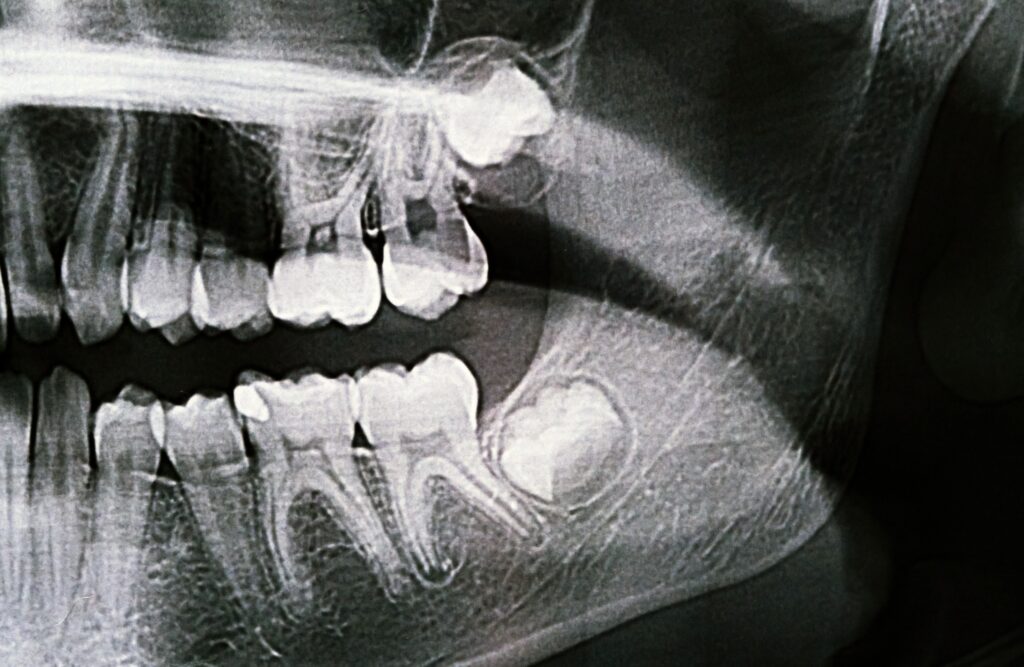

Wisdom teeth, also known as third molars, are the last set of teeth to emerge in the mouth, typically between the ages of 17 and 25. While some people have no issues with their wisdom teeth, for others, they can cause complications and need to be removed.

- Impacted wisdom teeth: This occurs when the wisdom teeth do not have enough room to emerge fully or are growing sideways, causing pain and discomfort.